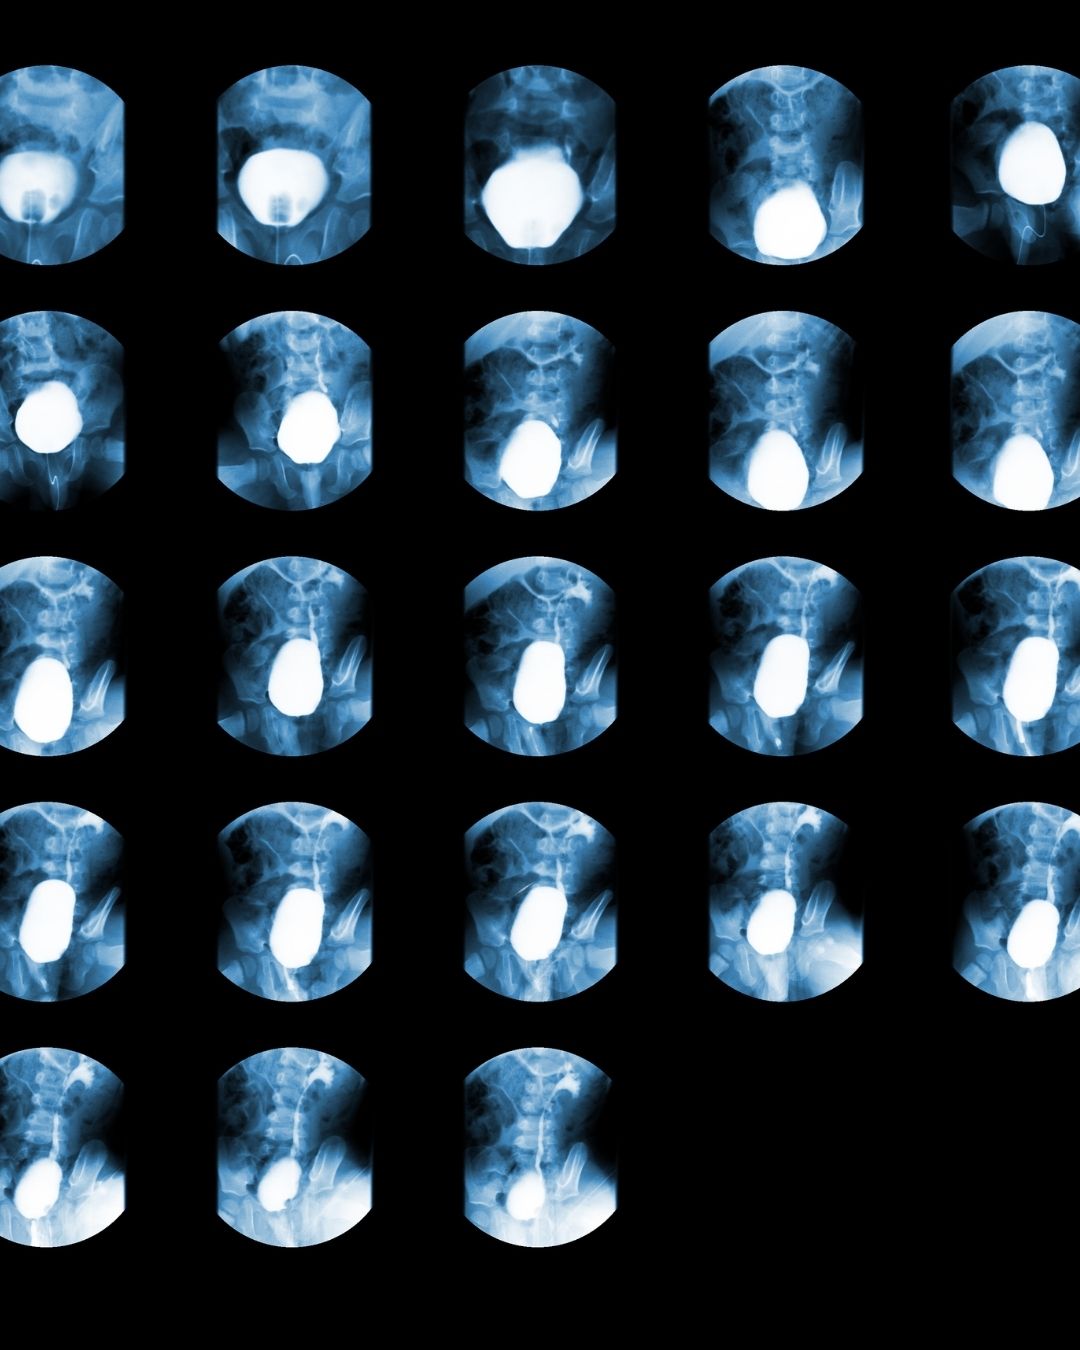

Voiding Grafi (VG), tıbbi literatürde genellikle “Voiding Cystourethrogram” (VCUG) olarak bilinir ve İdrar Yaparken Çekilen Röntgen Grafisi anlamına gelir. Bu görüntüleme yöntemi, özellikle idrar yolları ve mesane fonksiyonlarını değerlendirmek için kullanılır.

1. Hastanın mesanesine kontrast madde (radyoopak sıvı) yerleştirilir.

2. Röntgen çekimleri, mesane doluyken ve idrar yaparken alınır.

3. Böylece hem mesane yapısı hem de idrar akışı gözlemlenebilir.